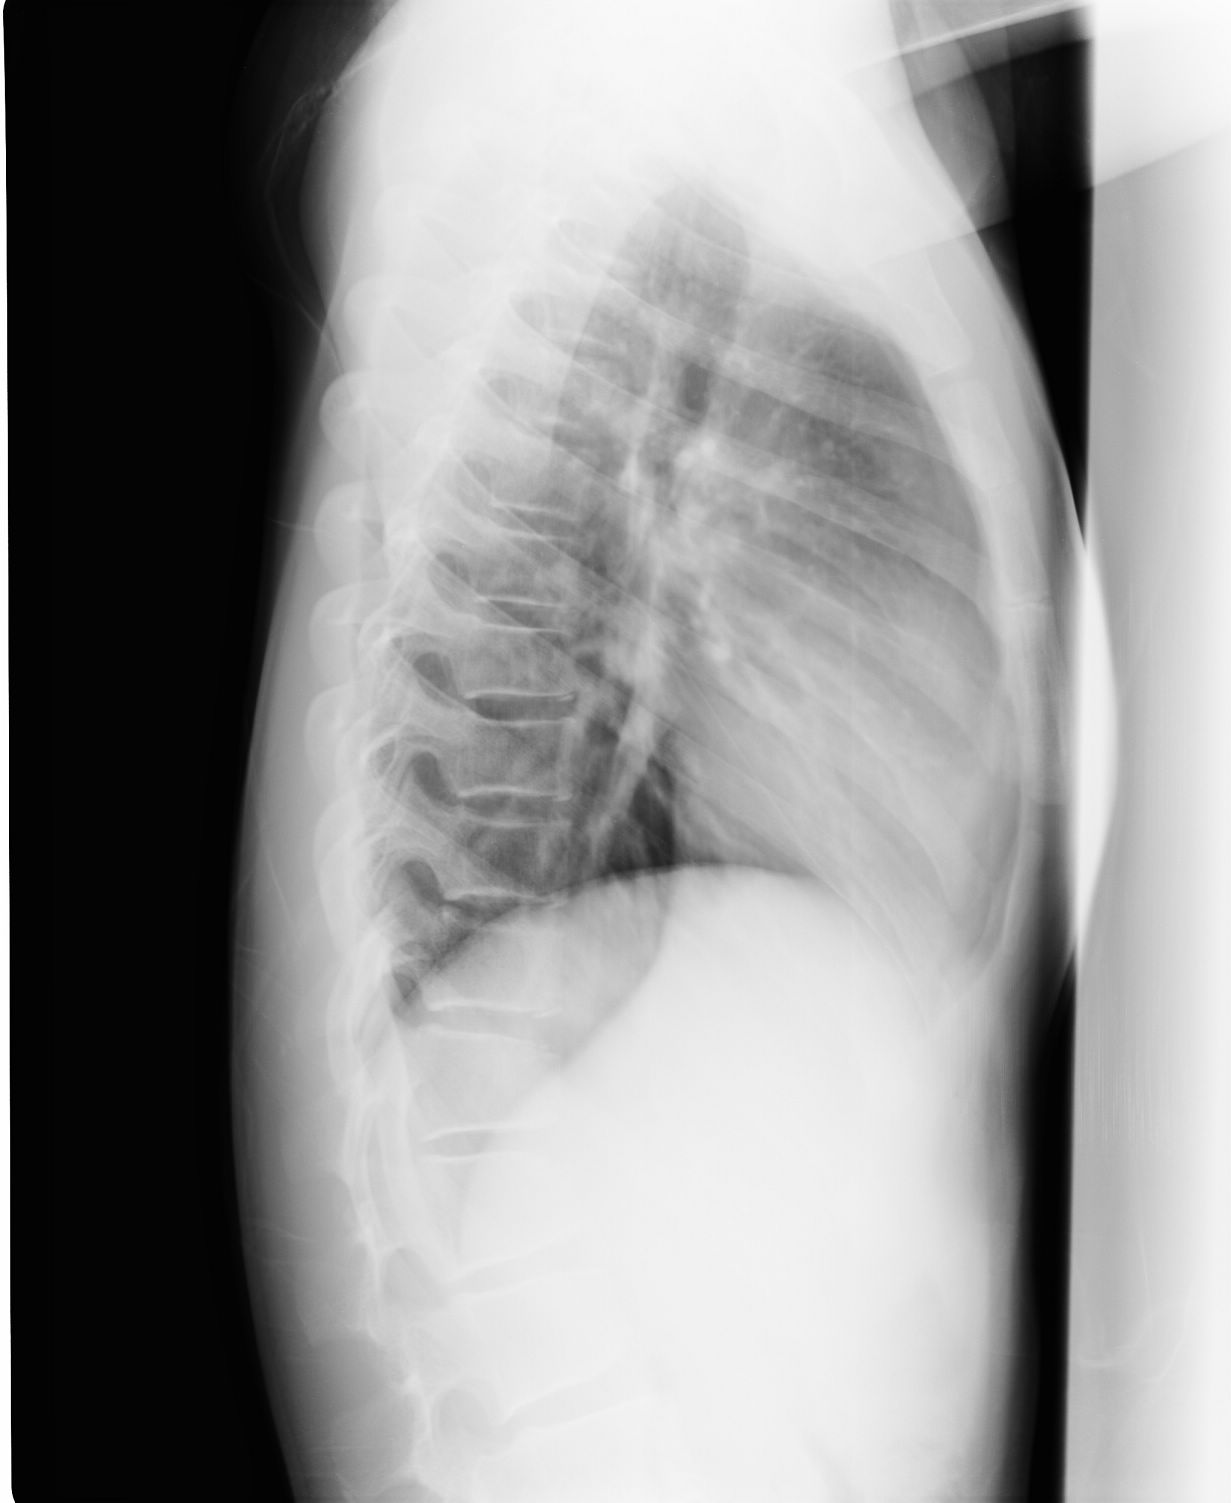

以下是引用黑白光影在2009-8-27 14:24:00的发言:[br]侧位显示胸腰段t12、l1、l2与其它椎体发育形态不一致,支持楼主考虑,建议作进一步检查确定。

以下是引用胡宇在2009-8-27 23:02:00的发言:[br][br] 骨质未见明显异常,学龄患者,要考虑长期伏案学习坐姿不正,继发肌肉及脊柱改变。带背背佳矫形试一试!t12、l1、l2椎体轻度楔变为应力性改变,很常见,不支持青年性驼背(椎体骺板骨软骨炎)。 [br]

以下是引用zxl51642在2009-8-27 12:04:00的发言:[br]骨质未见明显异常,学龄患者,要考虑长期伏案学习坐姿不正,继发肌肉及脊柱改变。带背背佳矫形试一试!t12、l1、l2椎体轻度楔变为应力性改变,很常见,不支持青年性驼背(椎体骺板骨软骨炎)。